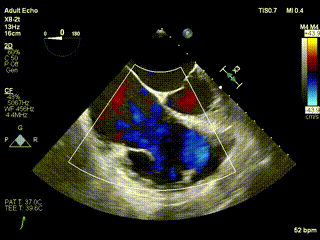

三例患者入院后,葛均波院士團(tuán)隊周達(dá)新教授、潘文志教授、張源博士、陳莎莎博士及心超室的潘翠珍教授、李偉教授對患者的情況進(jìn)行詳細(xì)評估和討論,最終決定為三例患者選擇LuX-Valve Plus40mm、50mm和50mm型號的瓣膜進(jìn)行手術(shù)治療。手術(shù)后即刻拔除氣管插管,術(shù)后患者三尖瓣反流癥狀得到顯著改善,復(fù)查心超結(jié)果顯示人工三尖瓣瓣膜支架固定穩(wěn)定,瓣葉關(guān)閉形態(tài)未見異常,未見明顯反流。